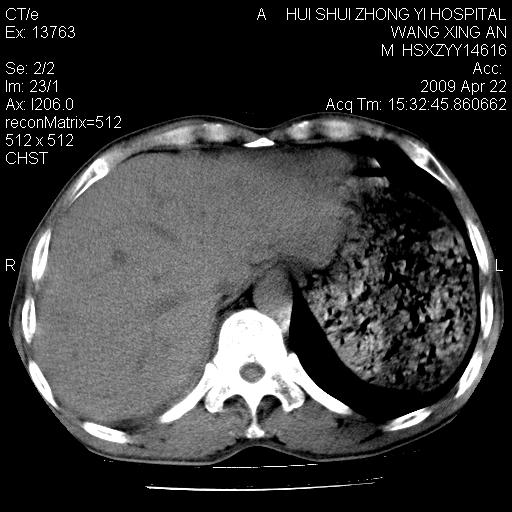

标题: CT19534:患者男、46岁咳嗽、胸痛半月。 [打印本页]

标题: CT19534:患者男、46岁咳嗽、胸痛半月。

1、右下肺中央型肺癌并右肺转移,右肺下叶不张。(肿块围绕右肺下叶支气管生长,致管腔闭塞右肺下叶不张;右肺有结节影)。

2、右侧胸腔积液。

3、右中上肺陈旧性肺结核(右肺见纤维化病灶及点状钙化)。

1)右肺中间段支气管癌并右肺下叶肺不张。2)右肺上叶、两肺下叶背段感染性病变。3)右侧少量胸腔积液。